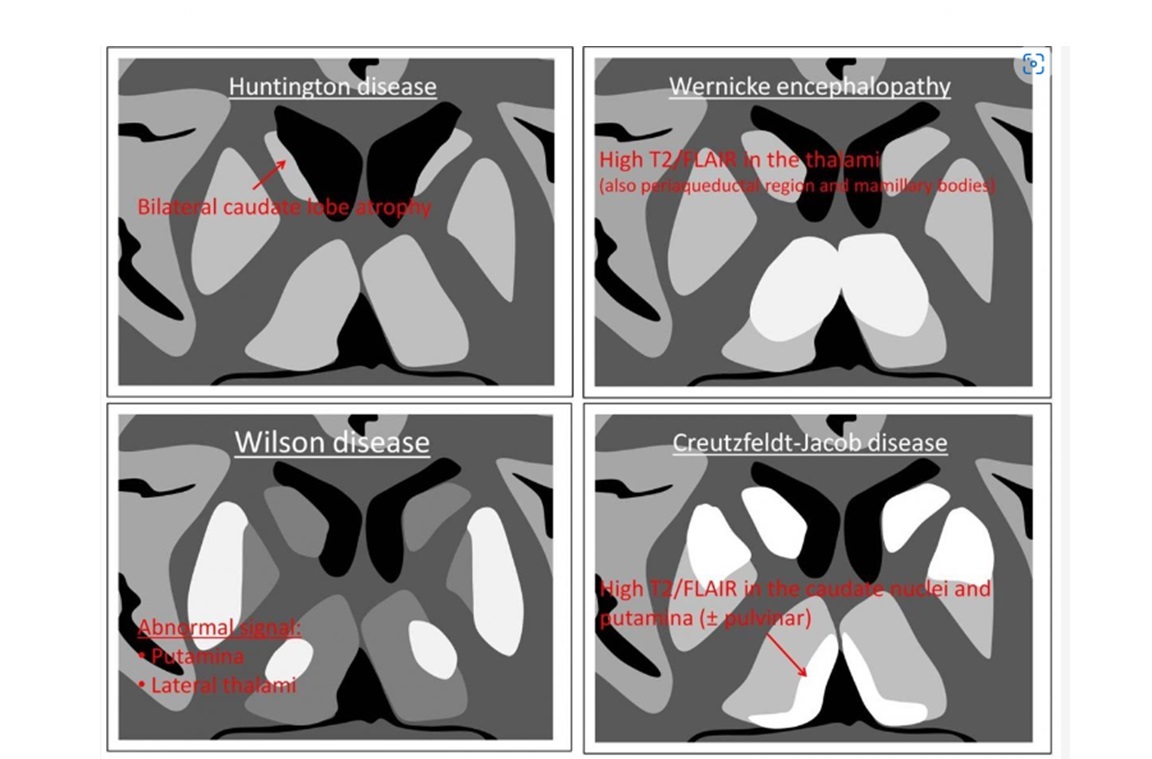

Increases T2 signal in bilateral medial thalamus and periaqueductal gray and enhancement of the mammillary bodies?

A

Wernicke

WW1

Remember wernickes is Thiamine deficency - T for thalmus

High T2/FLAIR on the dorsal medial thalamus, caudate lobe and putamina bilaterally with diffusion restriction?

CJD

Nb - called ‘ hockey stick’ sign

Also look for cortical gyriform restriction

WW3

C = caudate nuclei